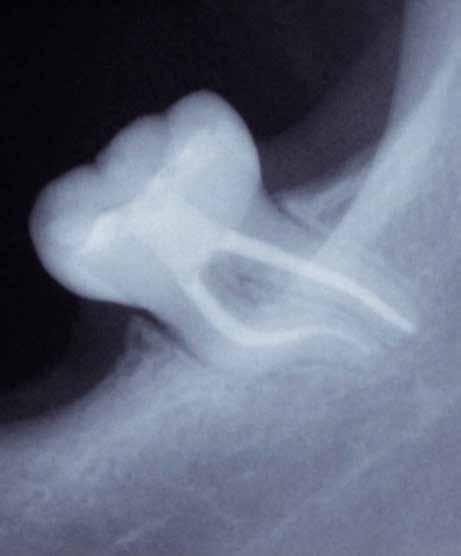

Hölgy páciensem az első konzultáció során tipikus kórtörténetet vázolt fel: Gyermekkora óta szeretett volna fogszabályozó készüléket, hiszen mindig is zavarta a class 2-es eltérésnél tipikusan jellemző nagy overjet (1-3. képek), és természetesen az ezáltal kifelé álló felső metszőfogai, részben a felső metszők protrúziója, részben pedig a disztálisan elhelyezkedő mandibula miatt. Annak ellenére, hogy több fogszabályozó szakorvosnál is járt az évek során, de mivel saggitális eltérése és az alsó metszőfogak torlódása miatt négy kisőrlőfog extrakcióját, illetve emellett sokszor állcsont műtétet is javasoltak neki, nem vágott bele a kezelésbe (4-5. képek).

A fogorvosa – nagyon helyesen – felhívta a figyelmét, hogy parodontális státusza is valószínűsíthetően romlani fog az eltérése miatt, újabb kört futott, immár 39 évesen, de még mindig premoláris fogak húzása és állcsontműtét nélkül szerette volna a fogszabályozást.